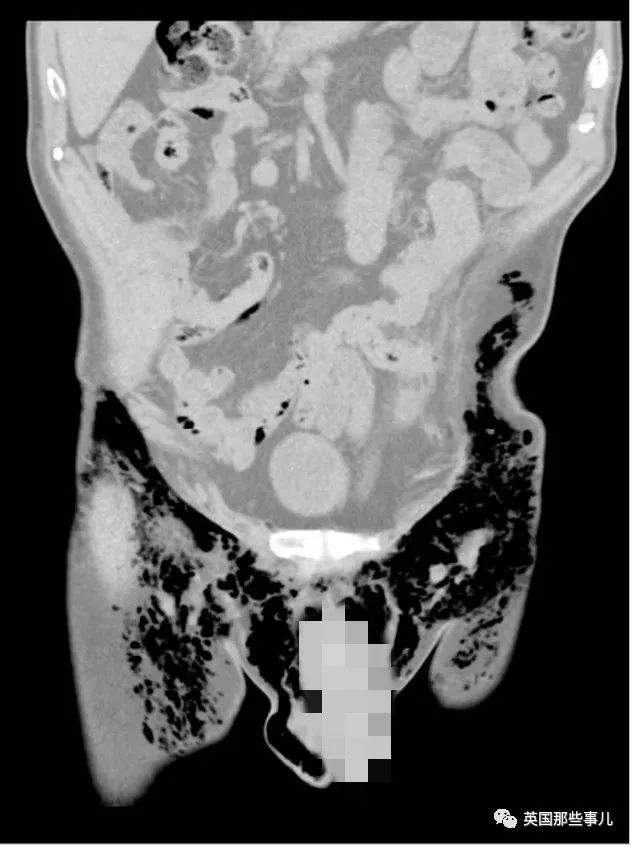

上图就是老爷子的CT片子。

等医生看到老人下半身的CT片子之后,意外地发现了老人DD会吹口哨的原因。

image

老人的大腿、下腹和阴囊内也有大量的空气

而阴囊左侧有一个很小的伤口,体内的空气顺着这个小口逃出体外,产生了跟吹口哨一样的效果。